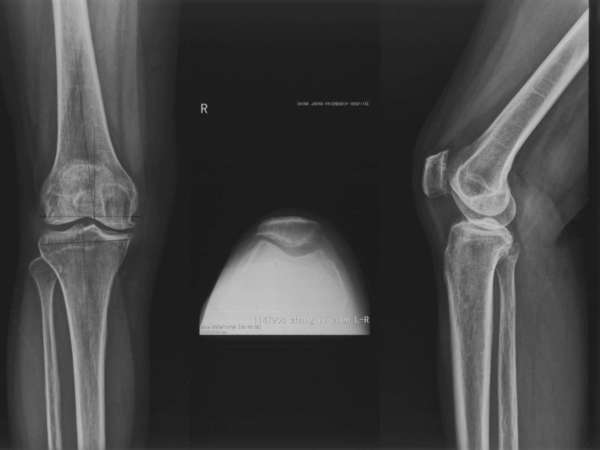

膝关节分为三个间室,分别为内侧间室、外侧间室、髌股间室。膝退行性关节炎可以影响其中任何一个间室,1/3的膝关节炎病人早期病变仅局限一个间室。目前治疗单间室关节炎手术方法有单髁关节置换 (unicompartmental knee arthroplasty ,UKA)、胫骨高位截骨(high tibial osteotomy, HTO)和全膝关节置换(total knee arthroplasty ,TKA)。胫骨高位截骨主要适用于年龄较轻、活动量大、体型肥胖的患者,并且该术式作为向全膝关节置换的过渡治疗术式,存在缓解症状不完全、疗效维持短的缺点,在年龄较大的人群中使用较少。而单髁关节置换术由于假体设计、病例选择、手术技术改进,越来越受到人们关注。我科自2003年起开展单髁关节置换术。现在的UKA手术效果令人鼓舞, Berge2005年报道Miller-Galante假体13年生存率为98%;。Cartier2007年报道161膝UKA10年生存率为94.5%;。我们科自2003年开始开展此项技术,早中期的效果良好。

对于髌-股关节退变的影响,存在的争议较大。我们在临床工作中很难找到纯粹的髌-股骨关节正常的患者,本组数据显示即使髌-股骨关节存在退变(Alhback 0-I期),没有持续的膝前痛史,不是UKA的禁忌。在我们的病例随访中,也发现了髌-股关节退变进展的现象,其长期的转归有待观察。